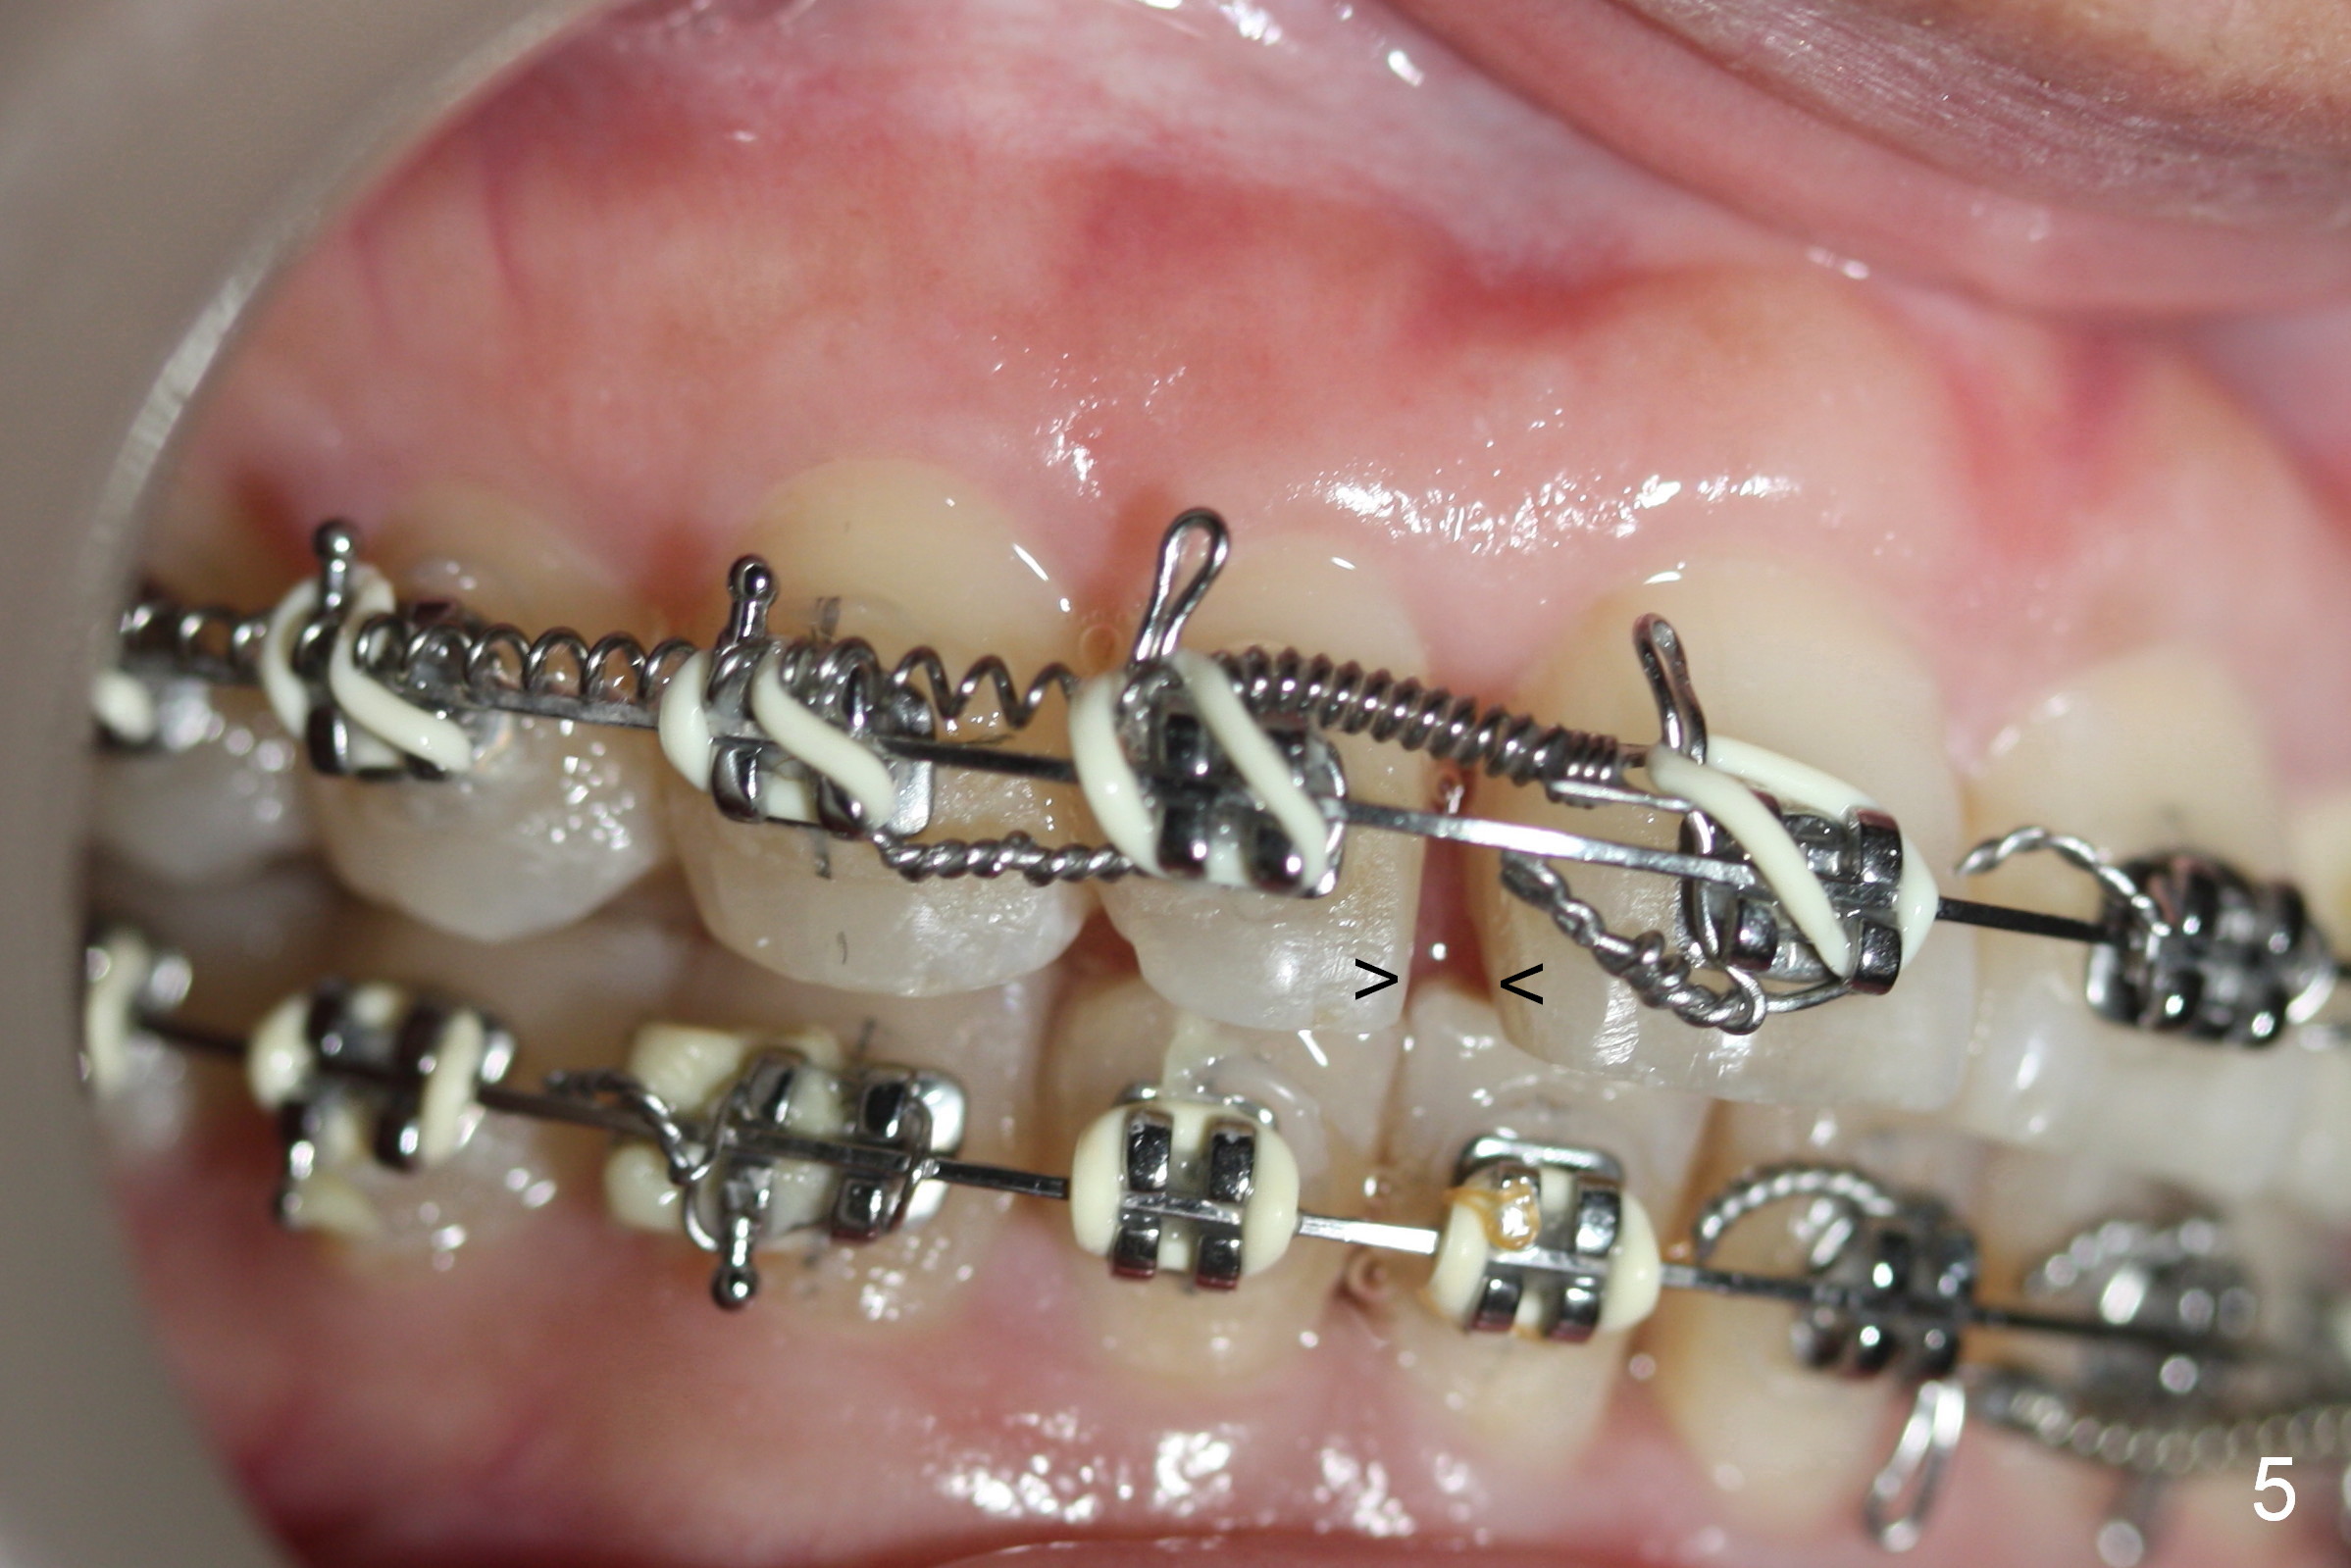

What has been done is arch wire sequence, proximal reduction and move the upper right teeth to the right (Fig.5) and the lower left teeth to the left (Fig.6) sequentially. It may be not enough when the unilateral Class II malocclusion is not addressed directly. Pay attention to the present occlusion now and address properly.